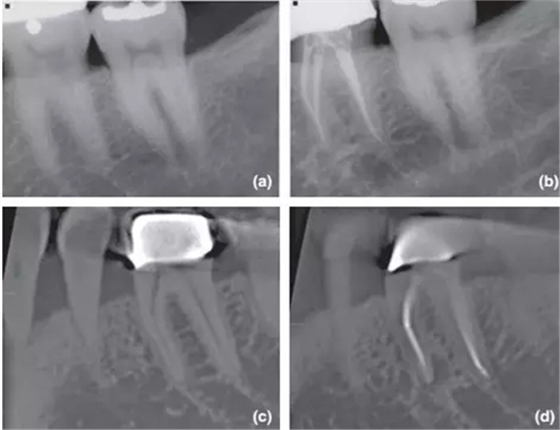

36術(shù)前X片,無(wú)根尖暗影;

1年回訪X片,根尖周無(wú)異常,診斷為成功的根管治療;

CBCT對(duì)同一個(gè)36進(jìn)行術(shù)前掃描,無(wú)根尖暗影;

1年回訪使用CBCT,發(fā)現(xiàn)新出現(xiàn)的根尖暗影,診斷為和X片完全相反的根管治療失敗。

CBCT掃描不受解剖噪點(diǎn)影響,對(duì)根尖周組織還原度高,而且還能做出精確的線性和容積測(cè)量,這些特點(diǎn)都十分有利于對(duì)骨損愈合的監(jiān)控。其中最具影響力的文獻(xiàn)當(dāng)屬由 Patel 在2012年發(fā)表的根管治療術(shù)后1年回訪臨床實(shí)驗(yàn),是第一篇應(yīng)用CBCT進(jìn)行術(shù)前及術(shù)后后掃描比較的研究。